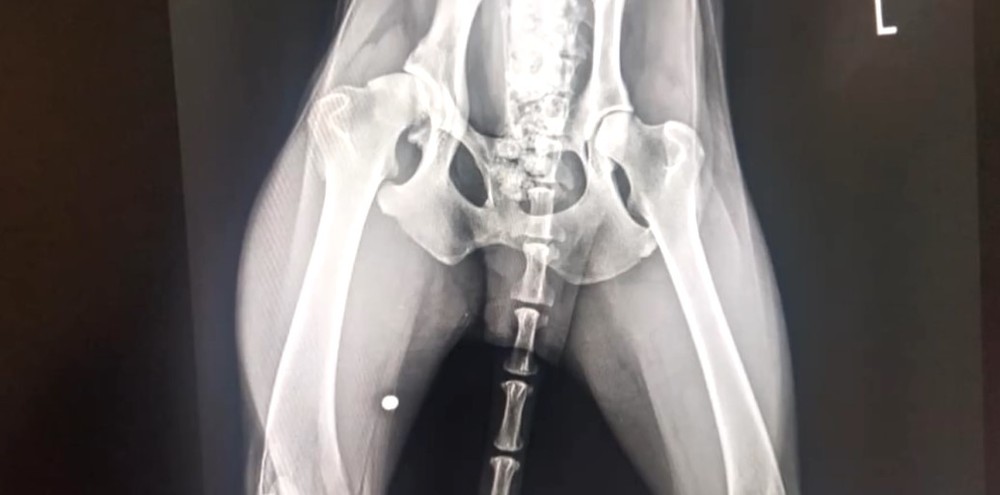

týraný psík

psik5